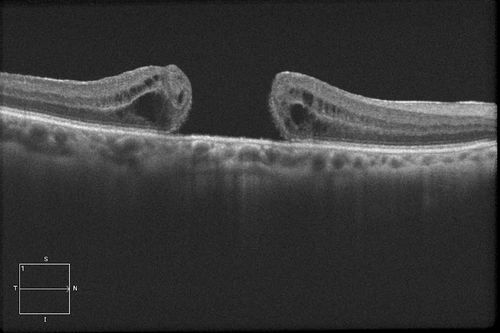

HD Grayscale OCT of Macular Hole

MACULAR HOLE

Mayo Clinic Jacksonville, Florida

Cirrus- HD OCT